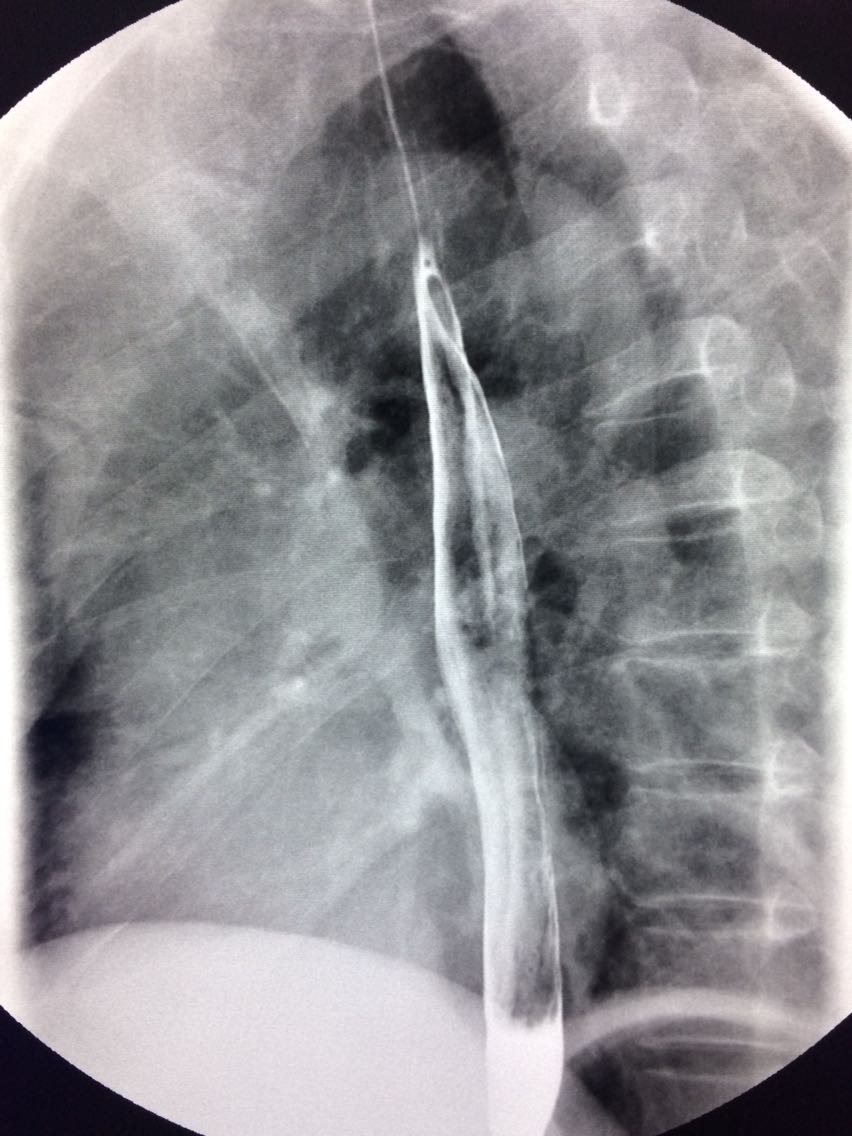

一例溃疡型胃癌。

男,45岁 反复胃疼5年余。 5年来,反复出现胃疼,进食后半小时加重,经常感觉饥饿,当地按胃溃疡,给予阿莫西林,奥美拉唑治疗,具体不详,效果欠佳,遂入院,入院来,饮食睡眠,二便可。 既往体健。 入院上消化道造影如图。

如图

讨论,诊断及鉴别诊断? 胃溃疡的影像表现? 溃疡良恶性的鉴别? 入院后行胃大部切除术。 诊断,胃腺癌。